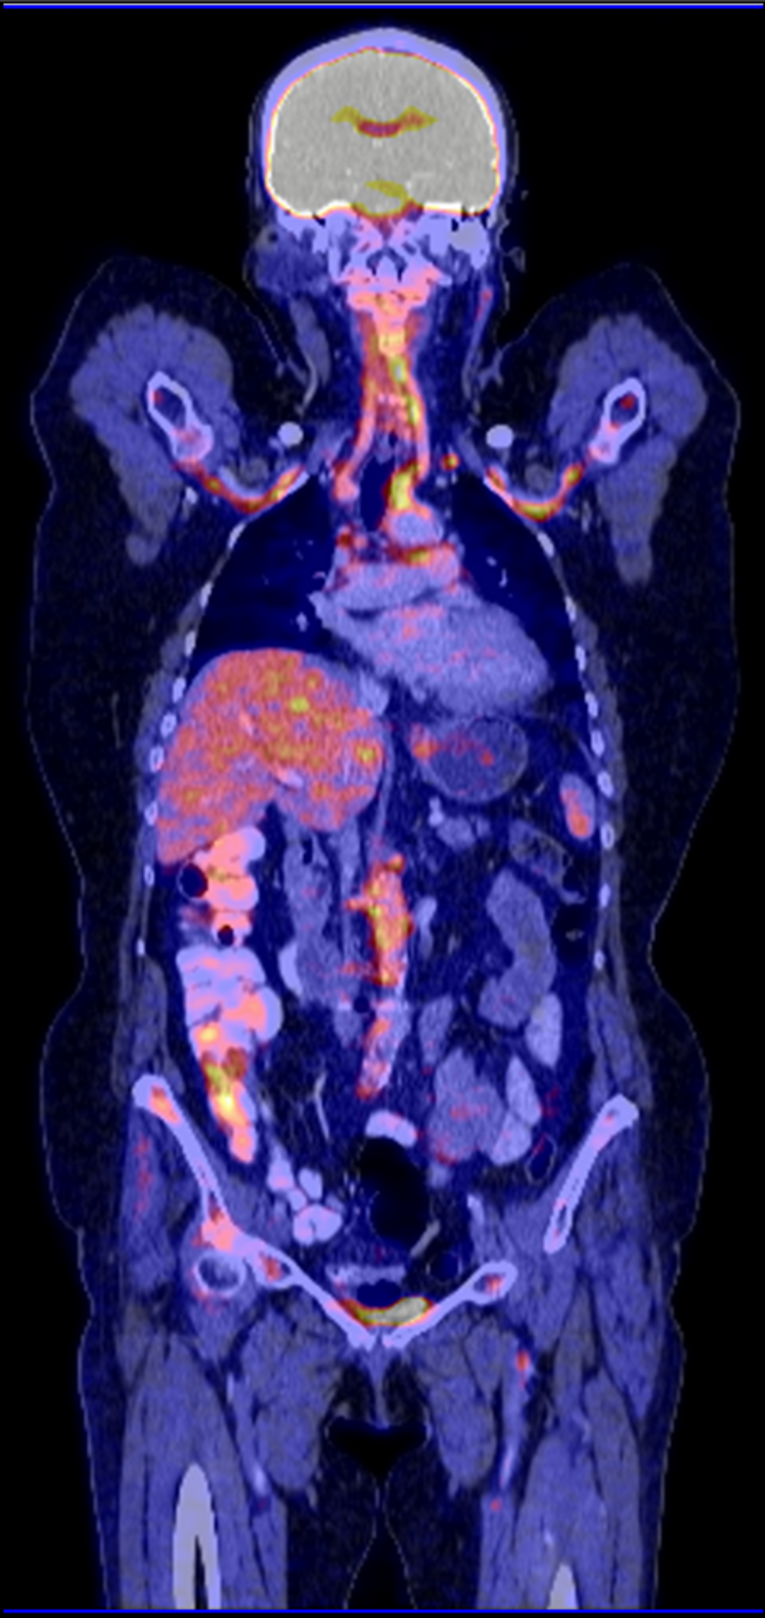

Die Diagnose wird durch die Entzündungszeichen im Blut und bildgebende Verfahren (Ultraschall, Magnetresonanztomgraphie und PET-CT), die die Gefäßveränderungen sichtbar machen, gestellt. Eine Gewebeuntersuchung der Schläfenarterie sichert manchmal die Diagnose endgültig.